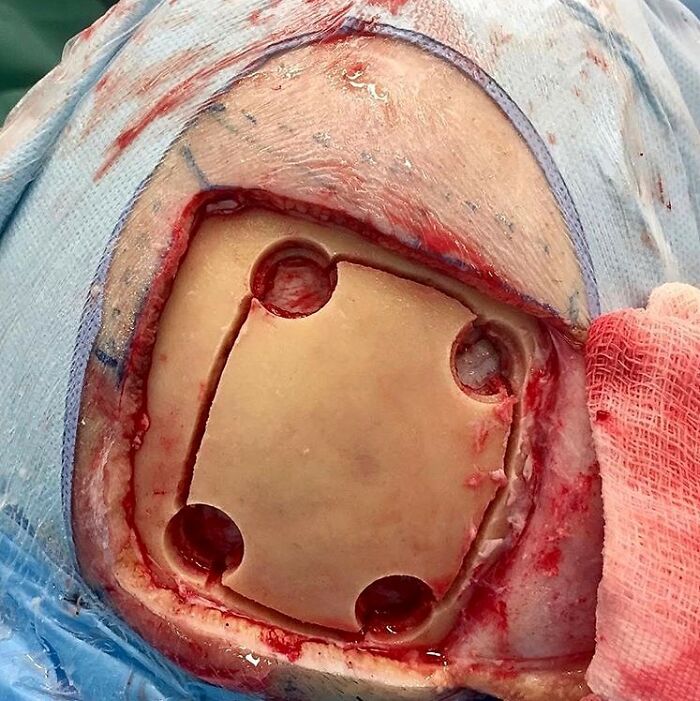

Putting That Skull Back In, Just Like A Puzzle!

The following picture shows the process of placing back a temporarily removed part of the skull, called craniotomy.

Craniotomy involves the removal of a segment of the cranium to gain access to the intracranial contents for brain surgery.

After a scalp incision is made, a burr hole is created using a high-speed drill. This allows for the removal of a bone flap, which is carefully preserved.

Following the bone flap removal, the dura mater is typically incised, providing access to the brain. Various surgical techniques are employed, depending on the specific pathological condition being addressed. These may include tumor resection, hematoma evacuation, arteriovenous malformation excision, or the placement of intracranial monitoring devices.

After the necessary intervention is completed, the dura mater is sutured or sealed using synthetic materials. The bone flap is then repositioned and secured using titanium plates, sutures, or wire mesh. The bone will eventually re-grow and the skull will be fully continuous again.

In certain cases, when the bone flap cannot be reattached, alternative synthetic materials (like a titanium mesh) may be used to reconstruct the cranial defect and replace the bone flap if it cannot be reattached.